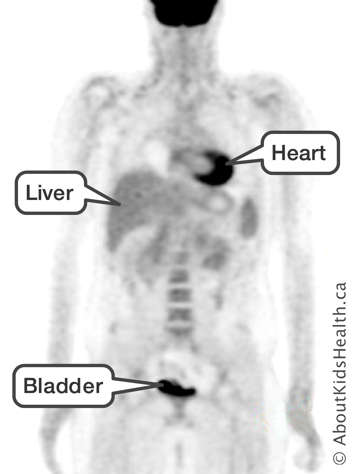

PET (positron emission tomography) scans take a picture that shows parts of the body where cells are burning lots of energy. Cancer cells use lots of energy to divide very fast, so they will show up easily on a PET scan.

You will need to lie still for an hour as the sugar travels to the parts of your body where the cells are very active. The glucose will have a radioactive tag attached to it. The sugar takes the radioactivity with it as it travels through your body. The scanner senses the radioactivity. The computer uses the radioactivity to make a picture that shows where in your body the cells are active and burning lots of energy.